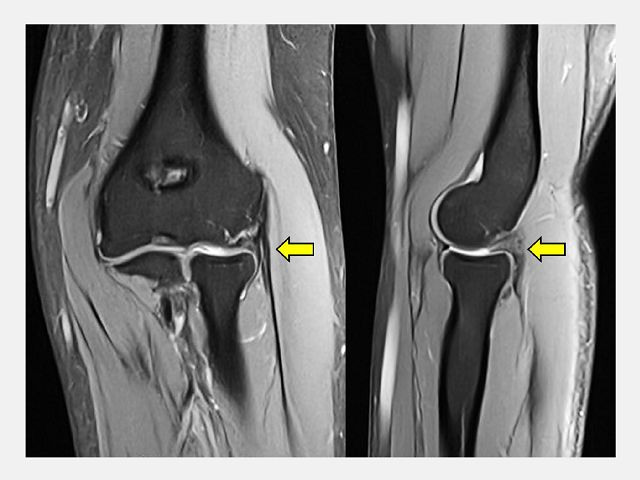

陳重宇醫師表示,C小姐經理學檢查及核磁共振(MRI)後發現,除了肱骨外上髁炎外,還合併肘關節滑膜皺襞增生與軟骨軟化。這類結構性病因若僅以「網球肘」的治療方式處理,往往難以根治。

陳重宇醫師說,外側手肘疼痛並非全是「網球肘」,其他常見原因包括:韌帶或關節囊損傷、剝離性軟骨炎、骨刺或退化性關節炎、滑膜皺襞症候群(synovial plica syndrome)和神經壓迫性疼痛。針對手肘的結構性病因,微創關節鏡手術是一個安全且效果良好的選擇。以C小姐為例,手術透過關節鏡直接觀察肘關節內部結構,精準鬆解發炎的肌腱附著點,並清除增生的滑膜皺襞。手術僅需數個約1公分的小切口,創傷小、出血少,術後疼痛明顯減輕,復原速度快。